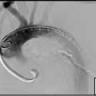

Percutaneous mitral repair using the MitraClip® system is a method derived from the edge-to-edge surgical procedure. The MitraClip® system replaces suturing with a clip to join the free edges of the opposing leaflets at the site of regurgitation.